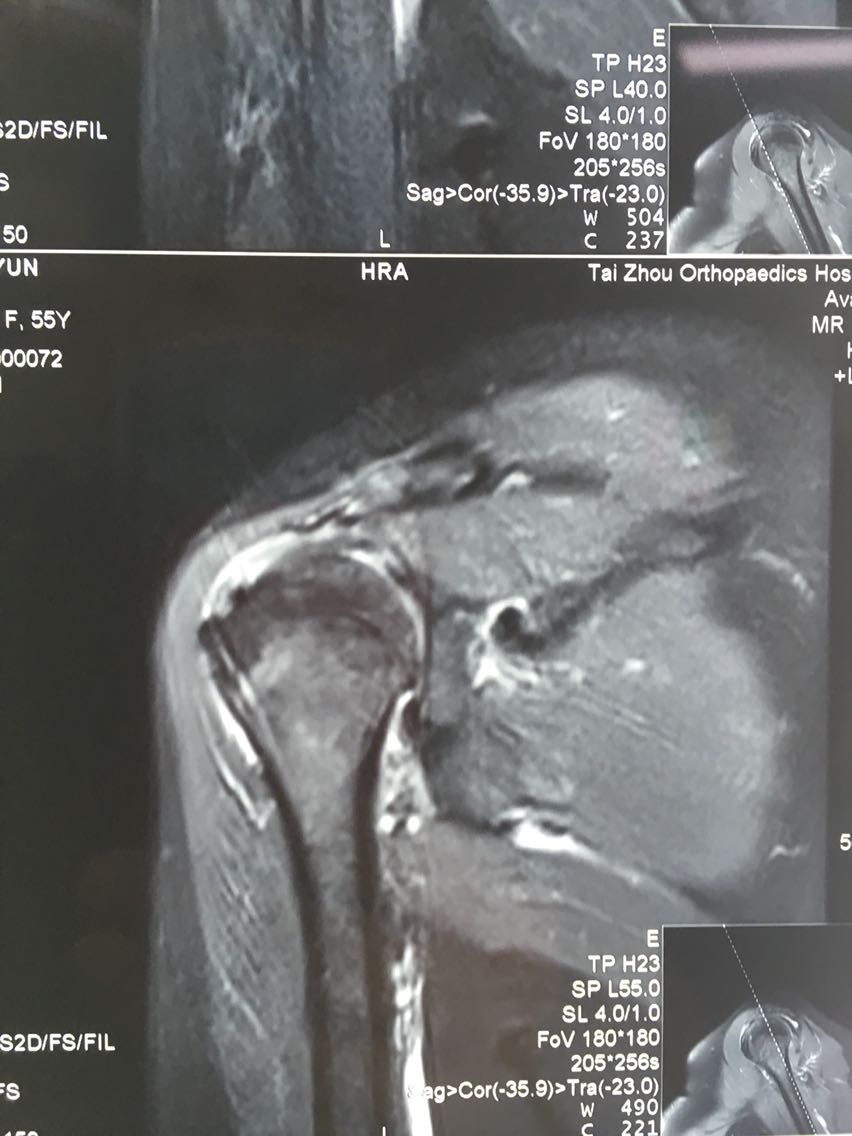

主诉:右肩关节疼痛、功能障碍6个月 现病史:患者于6个月前出现肩关节疼痛,以夜间明显,在当地医院诊断为肩周炎,给予指导关节功能锻炼,疼痛症状和功能障碍加重,效果不佳,来院就诊,核磁共振检查后,诊断为:肩袖撕裂 肩峰撞击症。收入院行关节镜下清理 肩峰成形 肩袖撕裂修补手术。

诊断:右肩袖撕裂 肩峰撞击症 冻结肩 治疗:关节镜下清理 肩峰撞击成形 肩袖撕裂修补手术。